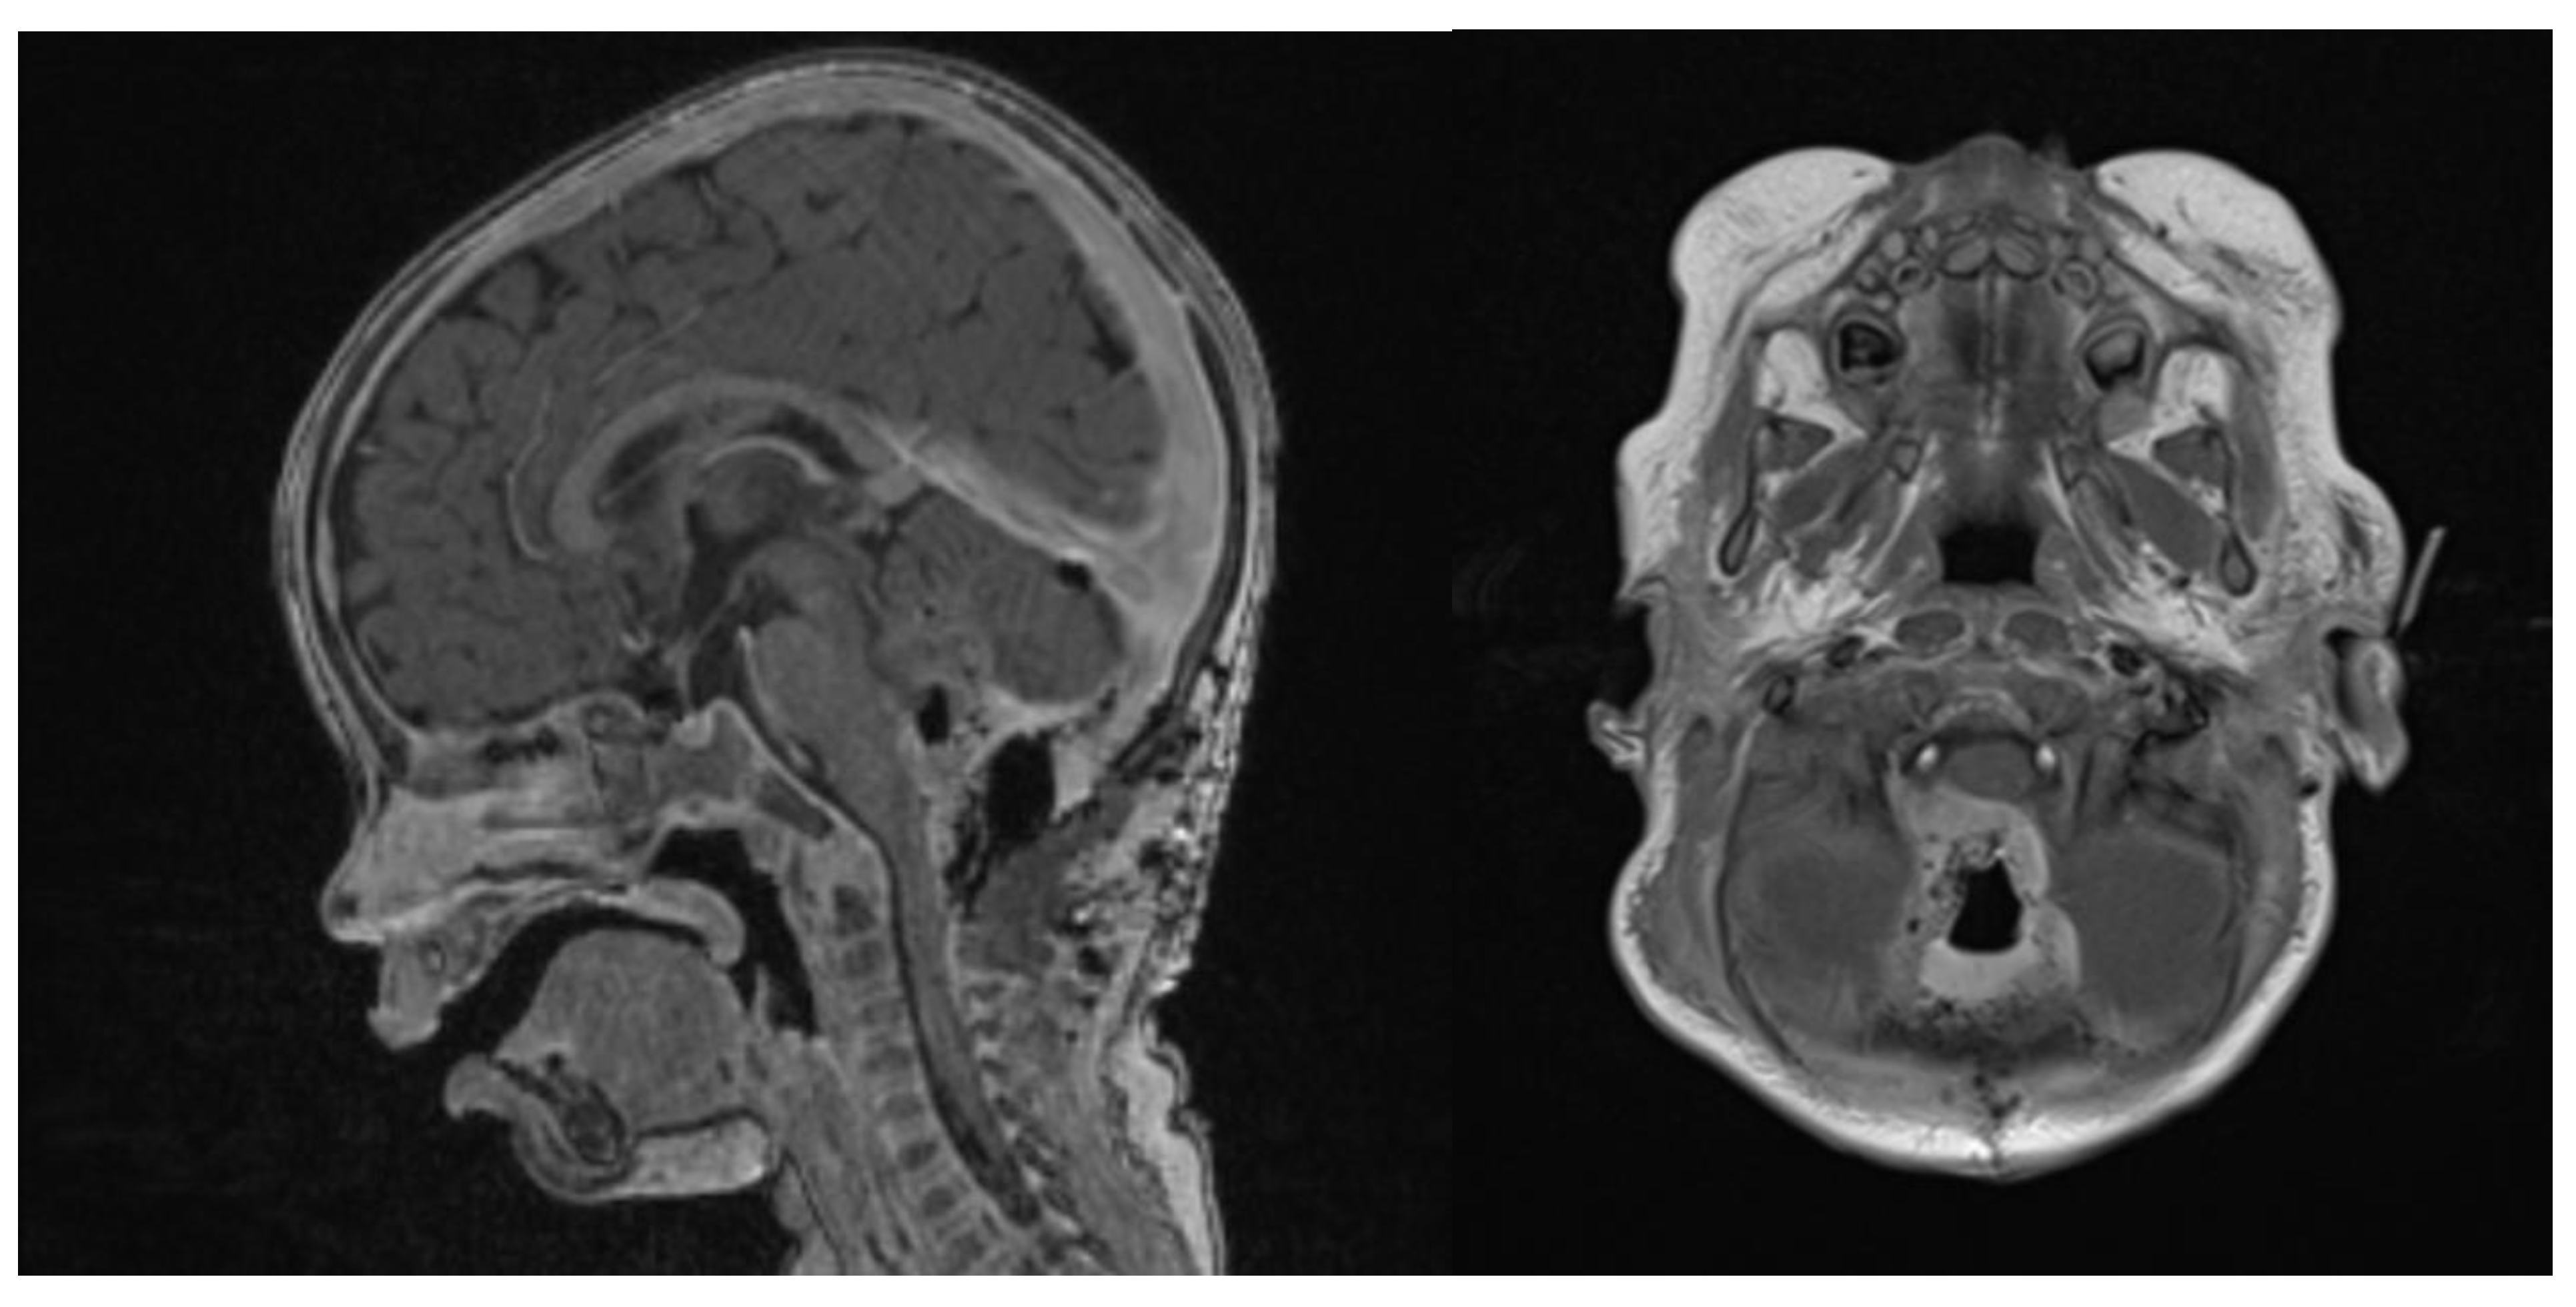

- Nowak, J.; Nemes, K.; Hohm, A.; Vandergrift, L.A.; Hasselblatt, M.; Johann, P.D.; Kool, M.; Frühwald, M.C.; Warmuth-Metz, M. Magnetic resonance imaging surrogates of molecular subgroups in atypical teratoid/rhabdoid tumor. Neuro. Oncol. 2018, 20, 1672–1679. [Google Scholar] [CrossRef]